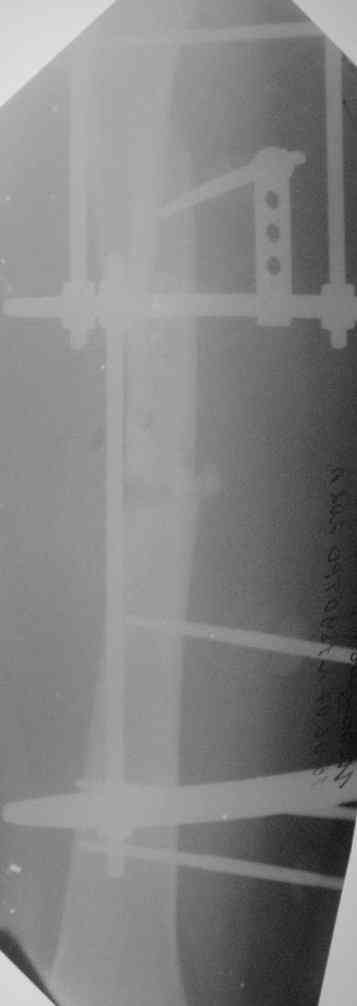

Молодой человек, 26 л., 6 месяцев назад получил перелом бедра. Вскоре присоединилась клиника жировой эмболии,

поэтому лечили аппаратом внешней фиксации. На сегодняшний день картина следующая(см. приложение)

В обсуждении предложены следующие варианты: 1) макс.дистракция в аппарате с переходом на дистрактор таз-бедро, штифтование сплошным титановым 12мм (более нет) гвоздем с рассверливанием. 2) дистракция в аппарате, окрытый синтез полым 10 мм гвоздем с минимальным рассверливанием. 3) снять аппарат, пластиковая повязка, подожать 2 мес., вернуться к обсуждению. Краеугольными вопросами дискуссии стали: 1)полый или сплошной? 2)открыто или закрыто (у нас нет ЭОПа, но большиство штифтований делаем закрыто)? 3) в какой срок после снятия аппарата можно штифтовать? Дорогие коллеги помогите определиться с тактикой, надеемся на Ваше компетентное, независимое мнение. Спасибо.